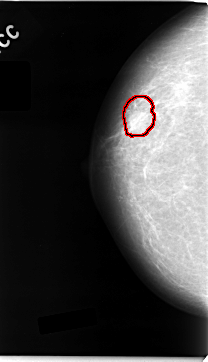

C_0035_1.RIGHT_MLO

RIGHT_CC LINES 4696 PIXELS_PER_LINE 2696 BITS_PER_PIXEL 12 RESOLUTION 50 OVERLAY

FILE: C_0035_1.RIGHT_CC.OVERLAY

TOTAL_ABNORMALITIES 1

ABNORMALITY 1

LESION_TYPE MASS SHAPE OVAL MARGINS MICROLOBULATED

ASSESSMENT 5

SUBTLETY 5

PATHOLOGY MALIGNANT

TOTAL_OUTLINES 1

BOUNDARY